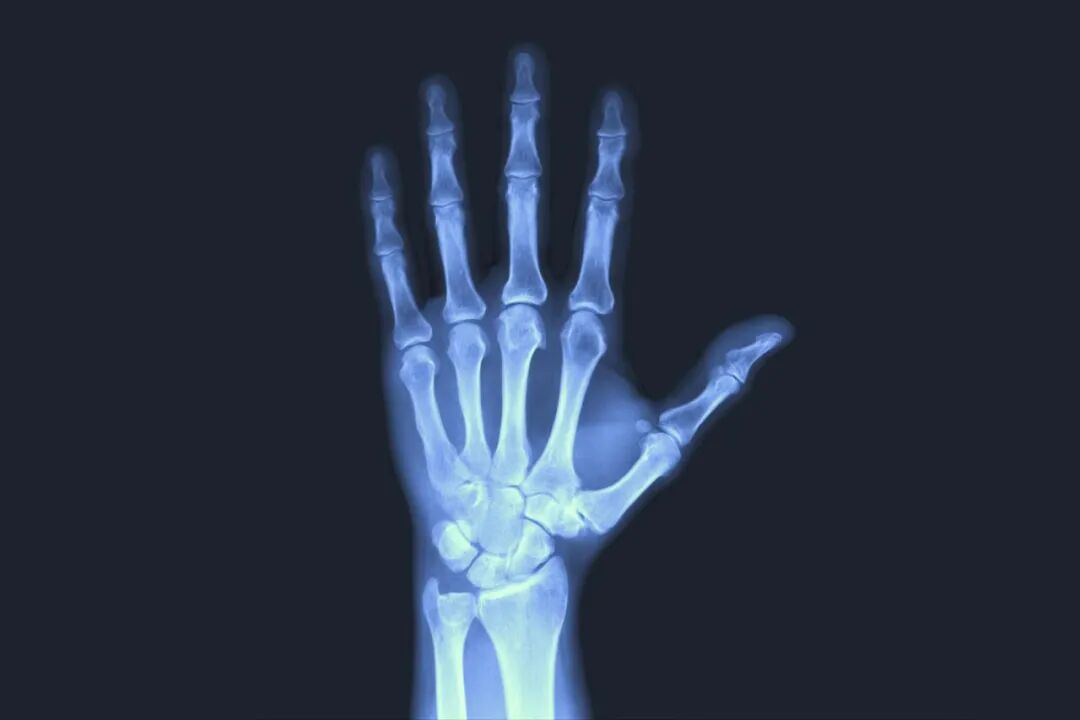

生长素治疗是一个连续的过程,频繁遗漏注射可能会影响治疗效果。因此,在非必要情况下,不建议随意停打生长素。 🟡 孩子生病:如果症状轻微且无发热,或者低热(体温<38.5°C),是可以继续使用生长激素的;如果孩子发烧,体温≥38.5℃,建议暂时停药,等体温稳定后再使用; 🟡 接种疫苗:生长激素治疗并不影响免疫系统正常功能,也不会增加疫苗过敏的风险,所以在生长激素使用期间,只要儿童身体状况良好且没有接种疫苗的禁忌证,可以正常接种疫苗,也可以继续生长激素治疗,无需停药; 🟡 意外骨折:对于意外骨折的孩子,建议停药3~4周,待断处骨痂完全融合后才可以继续用药[7]。